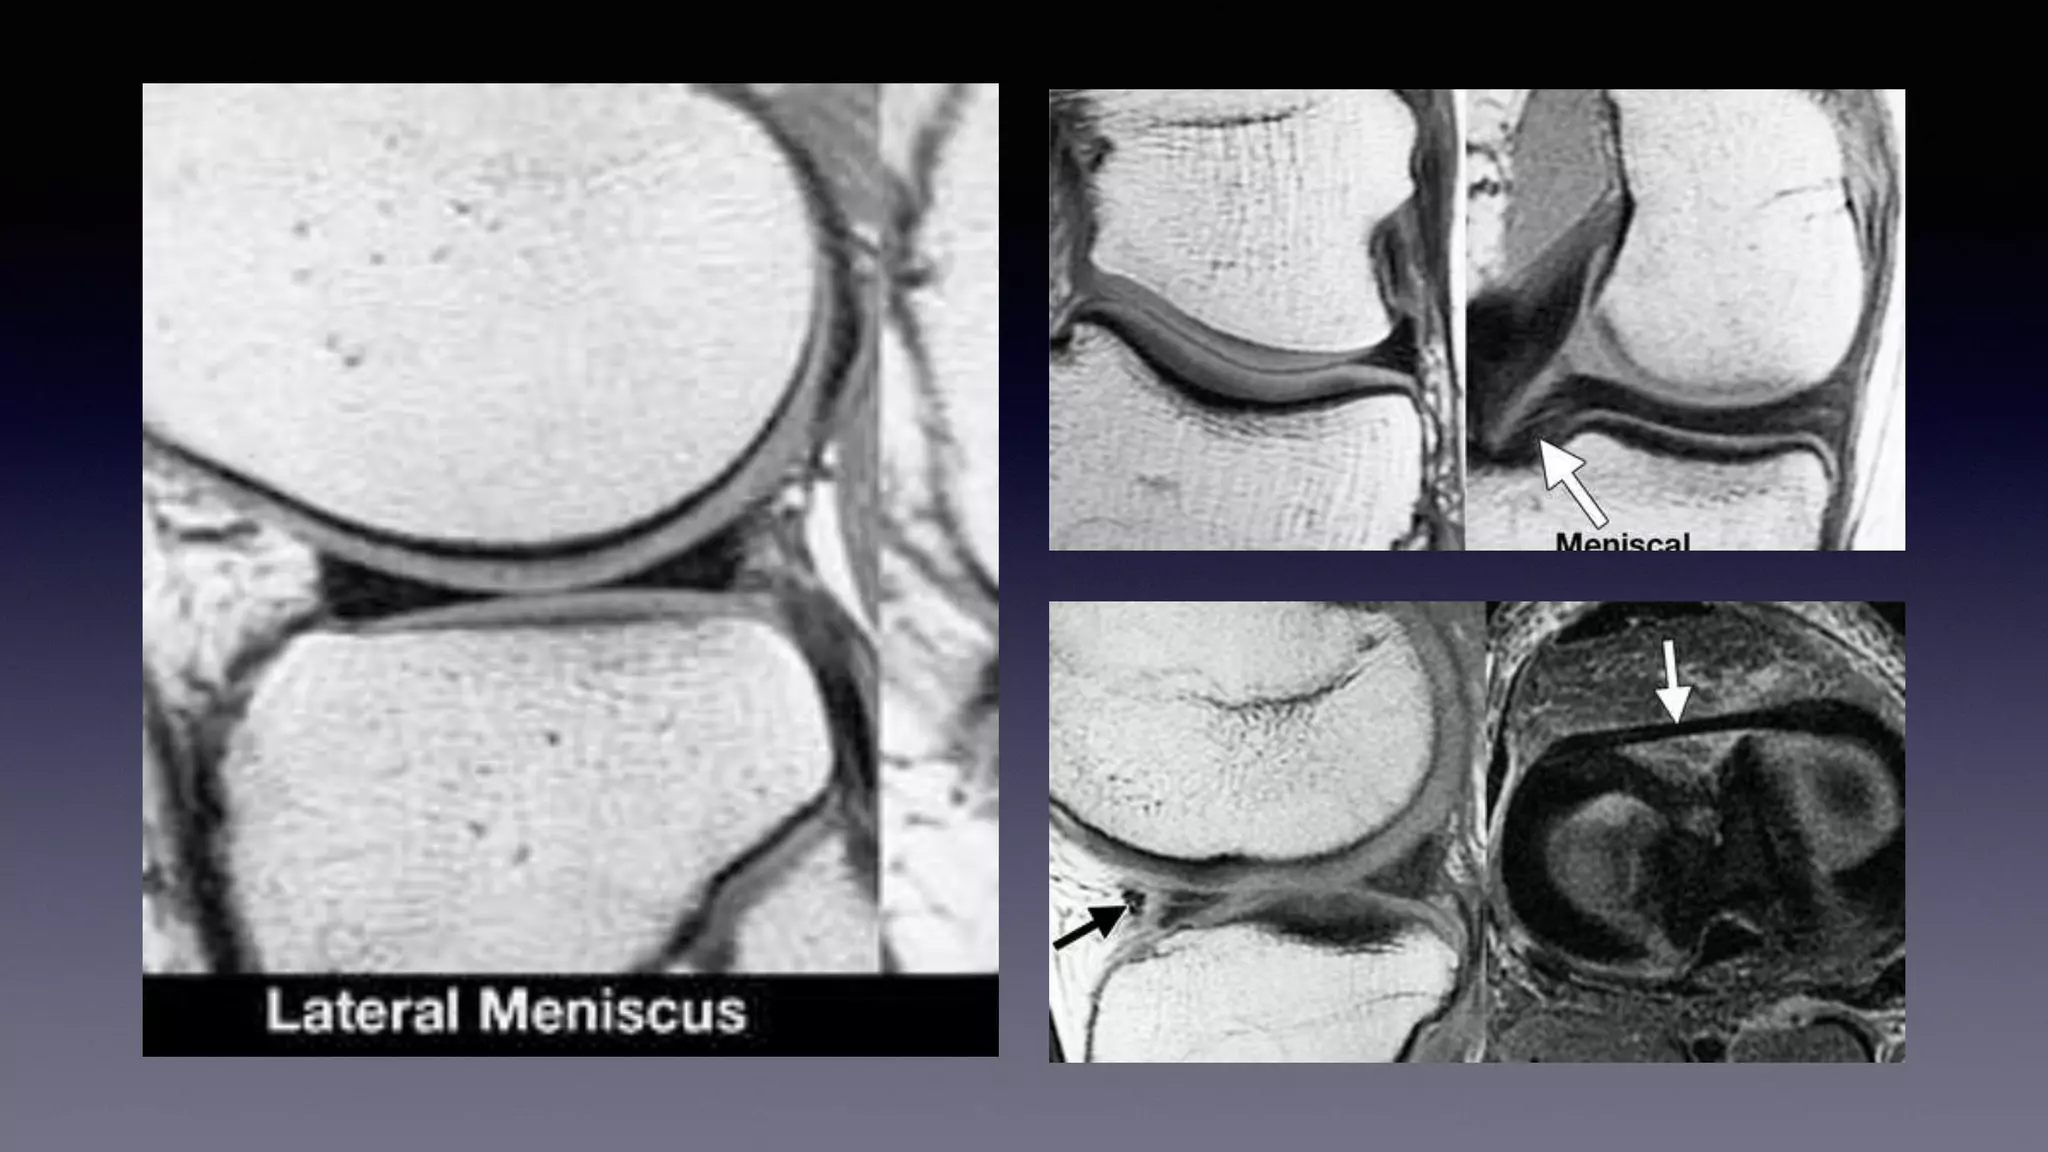

This document discusses using MRI to diagnose ligament injuries in the knee. It begins with an overview of MRI anatomy of the knee and expected pathology. It then discusses specific ligaments like the ACL, PCL, MCL and LCL. For the ACL, it shows images of acute tears, chronic tears and intrasubstance tears. It emphasizes knowing the knee anatomy well and correlating any abnormalities seen with clinical findings in order to apply the appropriate treatment.